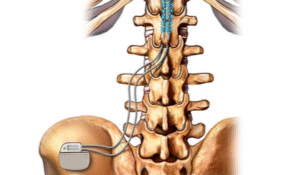

- Neuromodulation